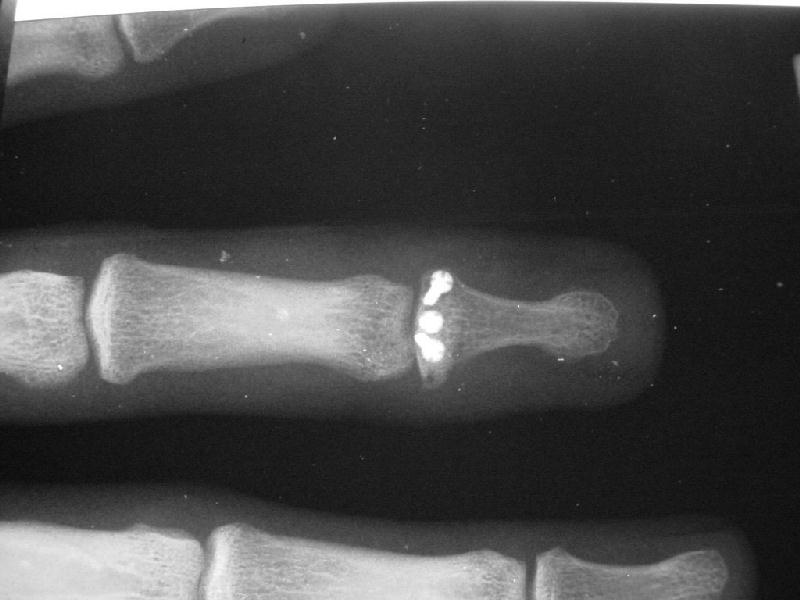

The injury:dorsal DIP fracture dislocation of the ring finger of a 16 year old male sports hopeful.

Unstable even in a well molded splint.